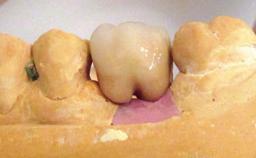

A 82-year-old female patient was referred to the Department of Oral Surgery and Stomatology at the University of Bern, Switzerland, for further diagnosis and treatment of growing discomfort in the right mandible (implant 45) and left maxilla (implant 23). The patient had had implants of various types inserted in the mandible and maxilla over the course of the previous three decades (in the 1980s and 1990s). The patient had received removable partial dentures on implants in the maxilla and on natural teeth in the mandible. The implants in the posterior right mandible had been restored with two splinted single crowns. The lower partial denture was not well tolerated by the patient and therefore had not been worn for over ten years. After insertion of the implants, there had been no complications for many years, but implants 45 and 46 as well as 23 had begun to exhibit signs of peri-implantitis with limited bone loss several years previously. The infection had been treated by the private practitioner, and bone loss around the three implants had not progressed until about half a year previously.